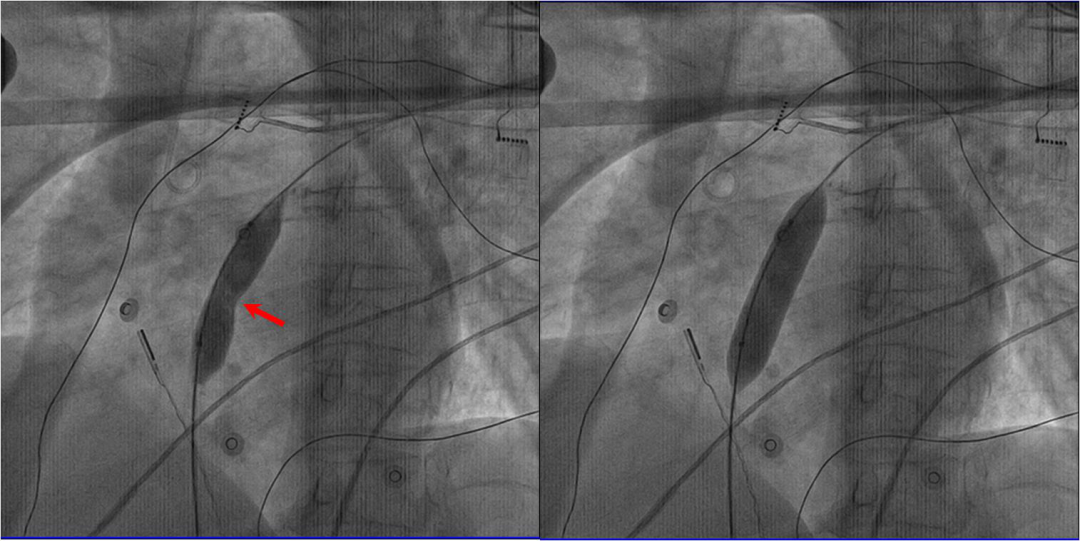

图解:射频房间隔造口术根据患者血流动力学参数进行个体化精准造口;红色箭头所示为扩张过程中球囊中央形成的“腰征”(左图),完全扩张后,“腰征”消失(右图)。